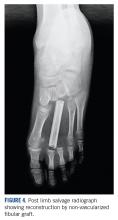

Surgery for metatarsal osteosarcomas can be challenging, as the compartments of the foot are narrow spaces with poor demarcation. Limb salvage surgery in the form of metatarsectomy needs proper preoperative planning and execution. Neoadjuvant chemotherapy will serve to downstage the tumor within the fascial barriers of the metatarsal compartment.It has also been postulated that osteosarcoma of the foot may have a better prognosis and survival compared to other osteosarcoma subsites. 10 This can be extrapolated from the fact that the majority are found to be low grade, and despite a long delay in treatment, there was no rapid increase in size and/or metastatic spread. However, tumor grade remains an important factor affecting survival— patients with higher grade tumors have worse survival. 8